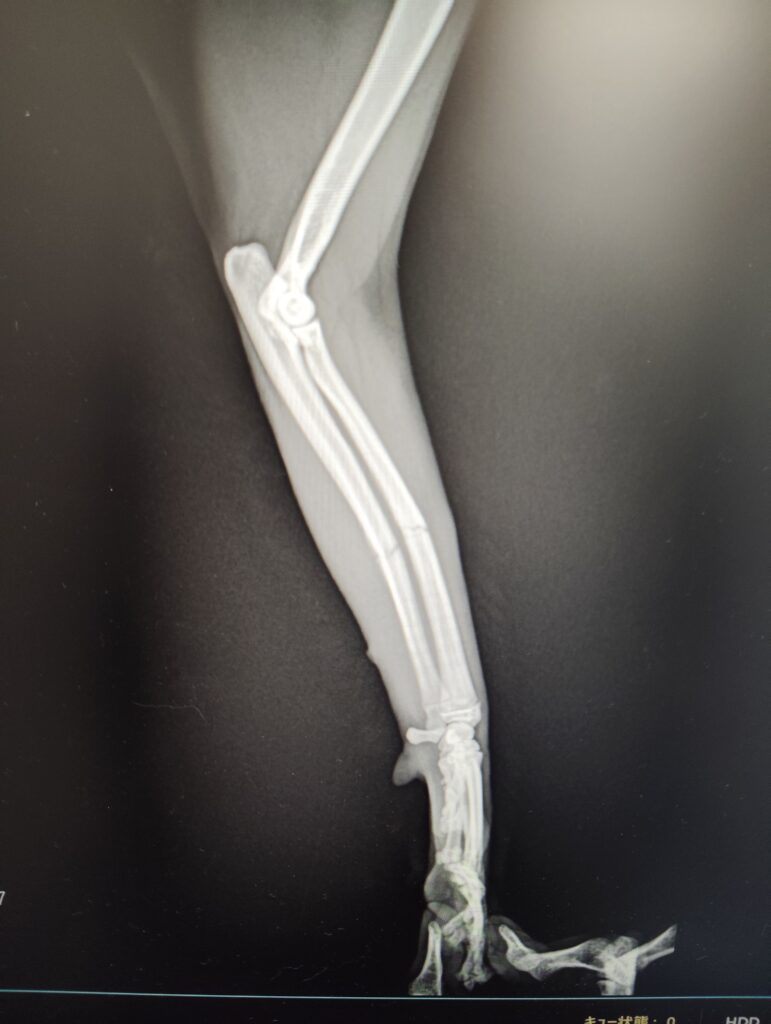

猫の橈尺骨骨折

日本猫、避妊メス、1歳

高所から落下後、前足を挙上

【レントゲン検査】

・左橈尺骨横骨折